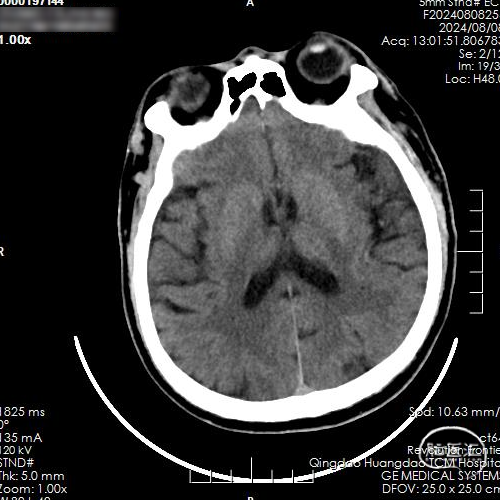

CT平扫:未见急性脑梗死早期病灶显影,未见大脑中动脉高密度征。

术后即刻复查脑CT,未见出血及梗死病灶。